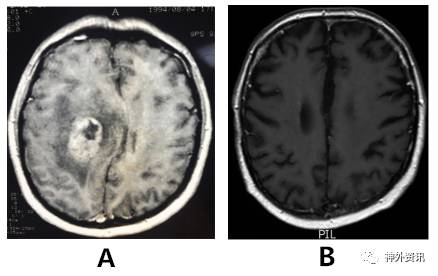

1994年,44岁的男性患者,因剧烈头痛伴左臂无力1月余就诊;头颅MRI成像显示右额后深部肿瘤(图1A),施行手术切除肿瘤。手术过程较为顺利,肿瘤标本的病理学诊断为多形性胶质母细胞瘤。术后患者接受全脑放疗和化疗。随访3周时发现左上肢无力症状消失。3月时头颅CT复查未见肿瘤复发。以后定期复查头颅MRI,均提示肿瘤未复发(图1B),直至2016年7月头颅MRI复查仍未见复发,而患者术后已存活22年。请3位神经病理学家复读病理组织切片,证实为典型的恶性胶质瘤。

图1. 患者术前与术后的头颅磁共振成像比较。A. 术前MRI显示肿瘤位于右额叶后部深处,增强扫描时呈强化灶,内有坏死区,周围脑组织水肿;B. 术后MRI复查未见肿瘤复发。